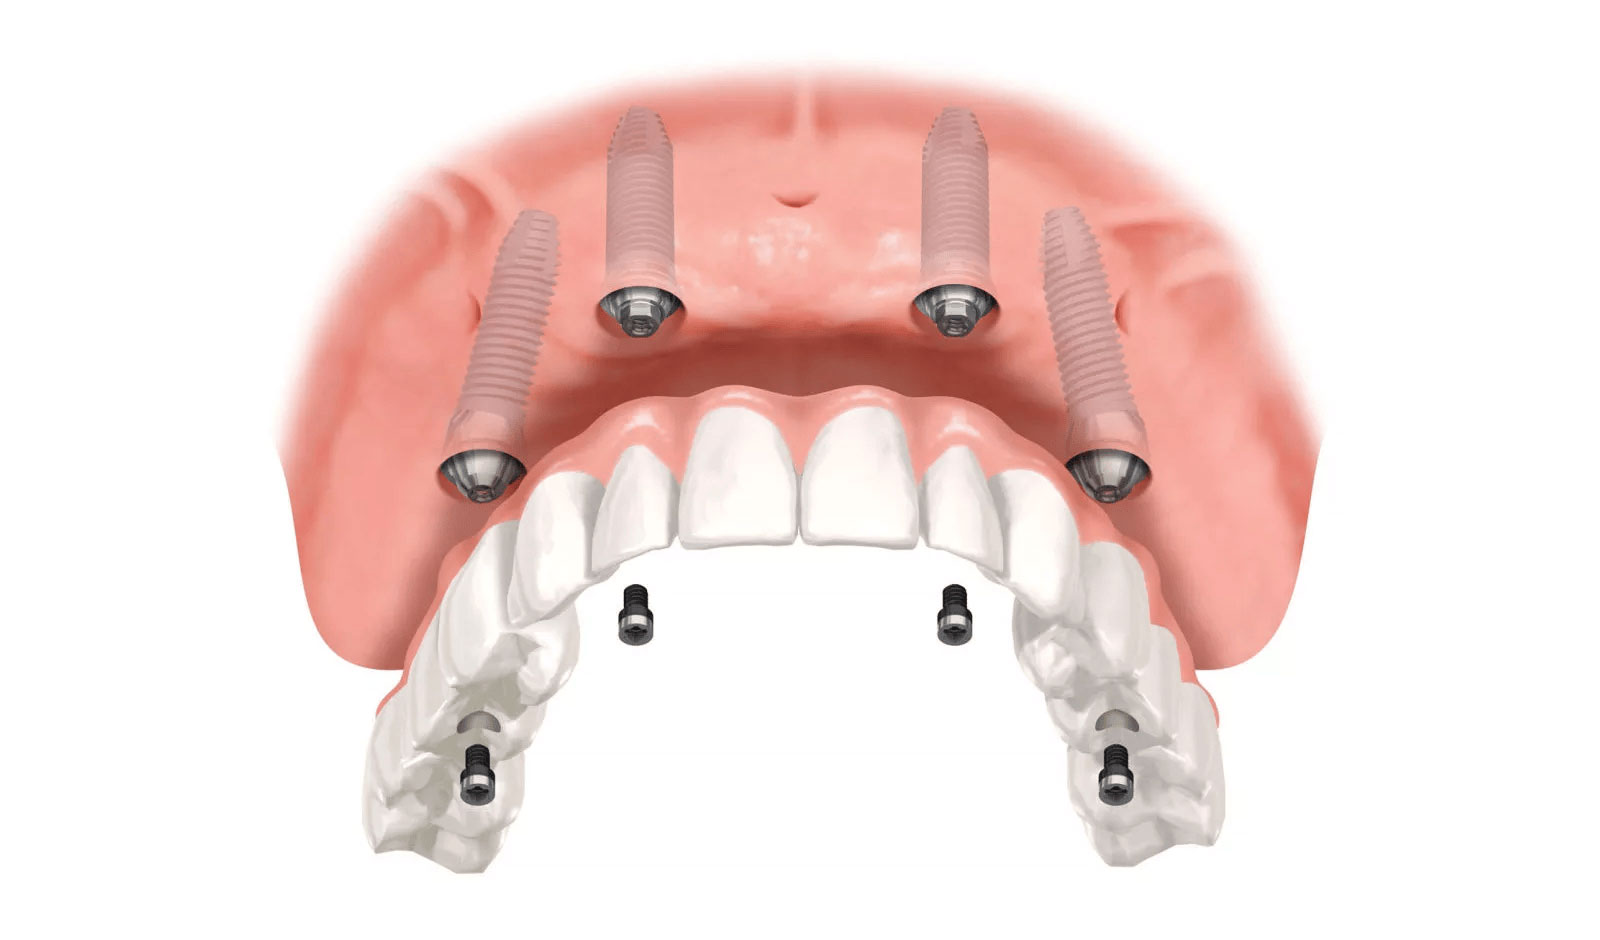

All-on-4とは、片顎につき最低4本のインプラントで、すべての歯を支える治療法です。必要なインプラントの本数を抑えながら、多くの歯を安定して支えることができます。

All-on-4では、骨が比較的しっかり残っている場所を選び、インプラントを斜めに埋入します。そのため、一般的なインプラント治療に比べて、必要とされる骨量を抑えやすい治療法です。